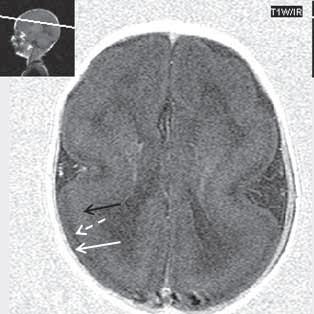

Zobrazení

CT je modalita málo senzitivní, prokáže ložiska denzity šedé hmoty mozkové, beze změn po aplikaci KL. MR je nejcitlivější zobrazovací metoda (optimální zobrazení šedé hmoty mozkové je technikou T1W + IR, naopak modalita FLAIR, velmi citlivá pro zobrazení změn bílé hmoty mozkové, nemá u heterotopie změny signálu nebo jen velmi diskrétní). Signálově ložiska heterotopie odpovídají šedé hmotě mozkové. Po aplikaci KL je beze

změn. Při ložiskové, subkortikální lokalizaci může být mozková kůra v jejich blízkosti zesílena, s projevy kortikální dysplazie.

Heterotopie šedé hmoty (subependymální forma) (šipka)

Obr. I.1.3c Heterotopie šedé hmoty (subependymální forma) (šipka)

Obr. I.1.3d Heterotopie šedé hmoty (subependymální forma); stejný pacient jako na obr I 1 3c

Obr. I.1.3e Heterotopie šedé hmoty (nodulární forma) (šipka)

Obr. I.1.3f Oboustranná subependymální heterotopie (šipky)